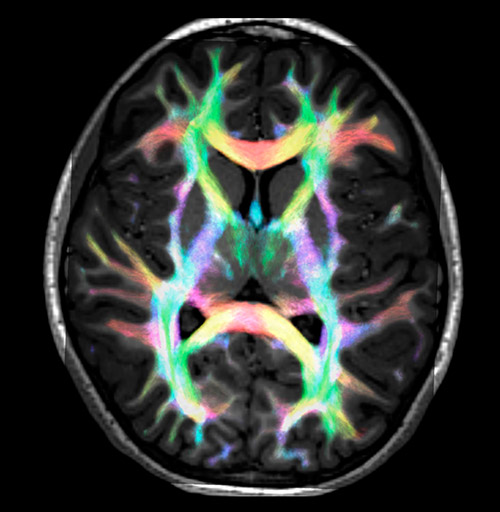

Fiber tracking from the left and right hippocampi to the fornix.

Fiber tracking from the left and right hippocampi to the fornix (green), and the corticospinal track based on a seed region of the posterior limb of the internal capsule.

Super-resolution directionally encoded color track-density imaging overlaid on T1-weighted structural MRI.